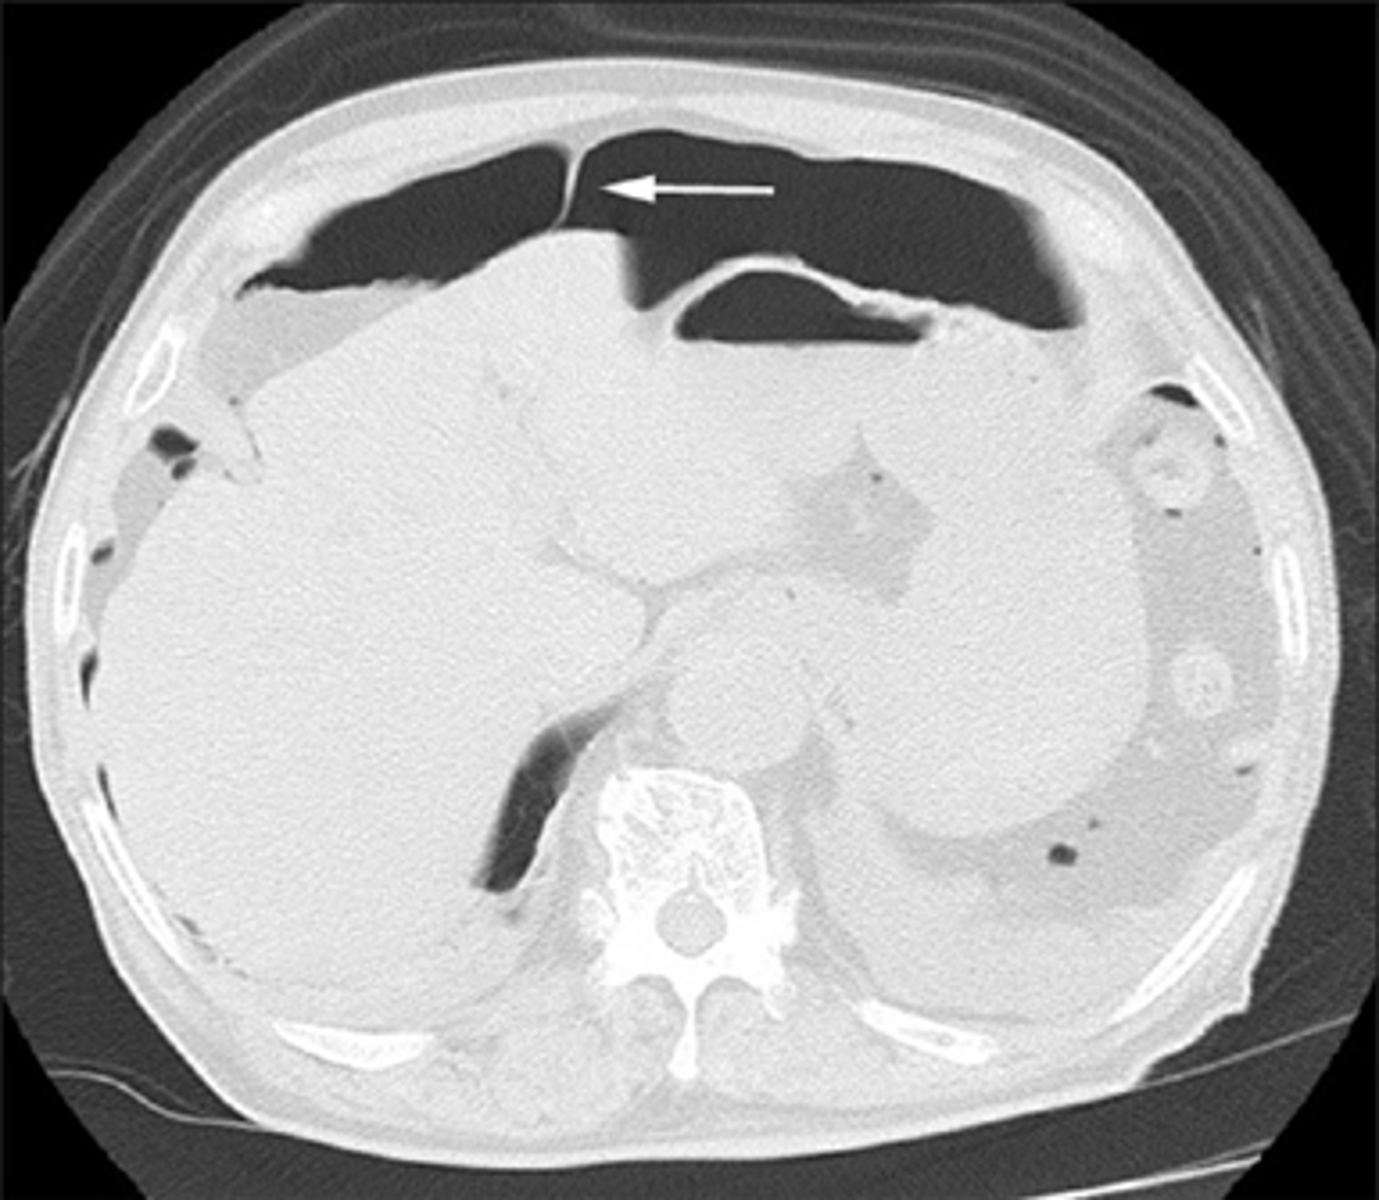

Free air seen on CT of upper abdomen.

WHITE ARROW:

Free air